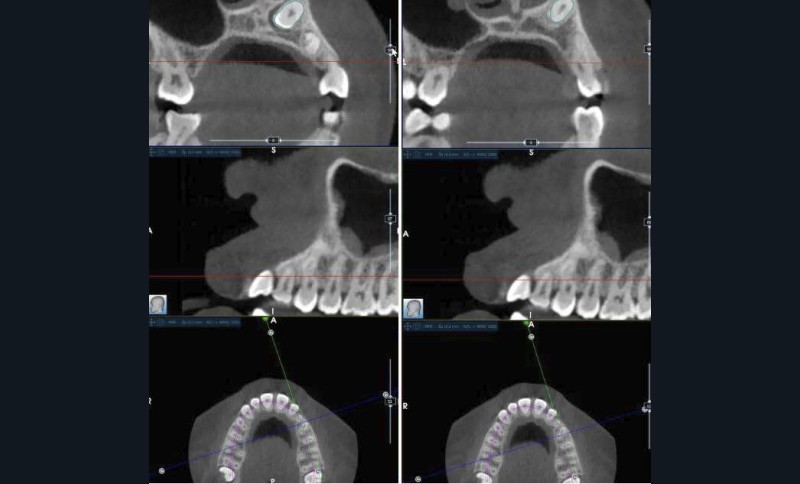

La radiographie panoramique permet de confirmer l’inclusion de la 23, apicale aux dents 21 et 22, ainsi que la présence d’un odontome en apical de la 63. Ces éléments nécessitent la réalisation d’un CBCT.

Le CBCT révèle une position très apicale de la 23. L’apex est fermé.

- mise en place de la 23 sur l’arcade par auto-transplantation étant donné la position très défavorable de la dent, associée à l’extraction de la 63 et de l’odontome ;